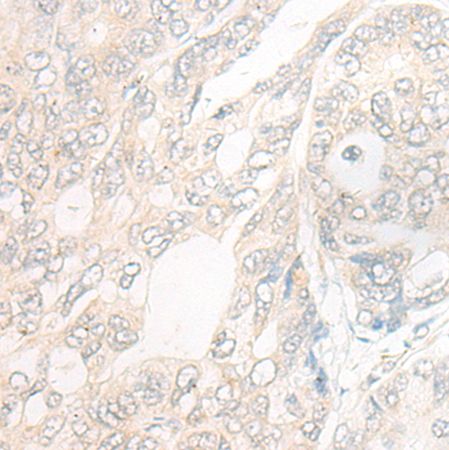

| IHCpositivecontrol: | HumancolorectalcancerandHumangastriccancer |

| IHCRecommenddilution: | 20-100 |